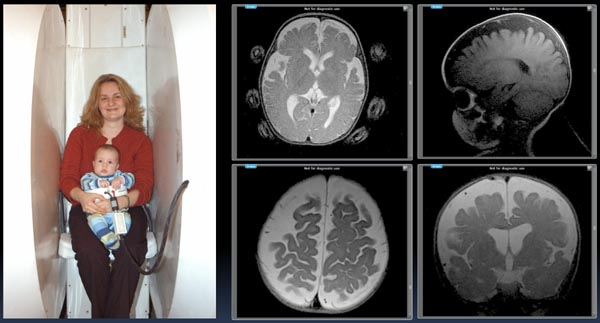

Figure 35.

Figure 36.

Figure 37.

Figure 38.

The Mommy and Me MRI produced the above (just obtained) infant pictures of a 7 month old child WITHOUT ANESTHESIA with the infant lying in the scanner in a Fonar receiver coil with the mother kneeling and facing into the scanner (opposite to the position shown) holding the child's head. The upper left image of the infant's brain shows the mother's head positioning finger-tips. The brain images obtained exhibit hydrocephalus in the infant together with pronounced CSF pooling suggestive of significant obstruction to the flow of CSF (most likely cervical obstruction) in and out of the brain generating increases in intracranial pressure (ICP) and cerebral pooling of CSF as visualized in the above brain images of the infant.